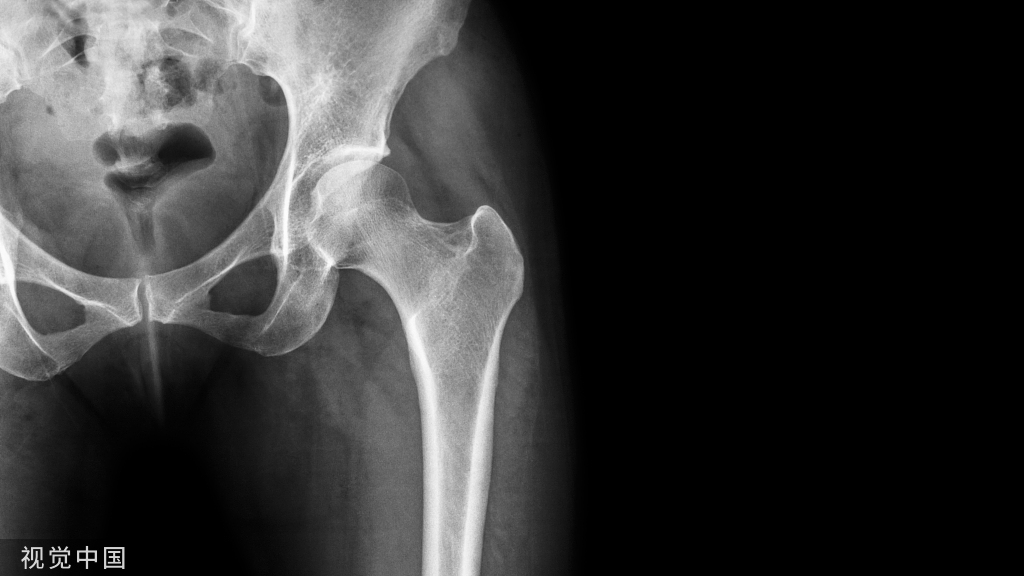

髋部骨折

二、髋部骨折术后患者翻身方法:

两人翻身法:1、操作者分别站在病人患侧的床边,先将病人的双手放于胸前,让病人屈曲健侧膝关节,操作者一人双手分别放至病人的肩和腰部,另一人将双手分别放至病人的臀部和患肢膝部,并让病人健侧下肢配合用力,同时将身体抬起移向患侧床沿。

2、让病人稍屈曲健侧膝关节,在两膝间放置2-3个枕头,高度以病人双侧的髂前上棘之间的距离再加上5厘米,操作者一人双手分别放至病人的肩和腰部,另一人双手分别放置臀部和患肢膝部同时将病人翻向健侧,将患肢置于两膝间的枕头上,保持患肢呈外展15-20度、屈髋10-20度、屈膝45度,然后在病人的背部垫一软枕,胸前放一软枕放置上肢。